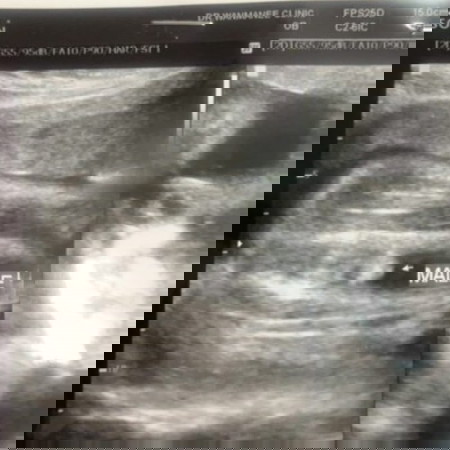

เป็นเด็กชายชัวร์ๆมั้ยคะแม่ๆ 😂😂

ไปหาหมอแต่ละเดือน ทักไม่เหมือนกันสักรอบ เดี๋ยวเด็กหญิง เดี๋ยวเด็กชาย 😅😅 แต่ทุกคนที่เข้าทัก ย้ำว่าทุกคน 😂😂 มาลูบท้อง ทั้งๆที่บางคนไม่รู้จักกันด้วยซ้ำ ก็ทักเป็นเด็กหญิง ตัวแม่เองไม่มีสิวสักเม็ด ผิวใส ไม่มีอาการแพ้ อยากกินแต่ของหวาน ท้องไม่แหลม เหมือนที่ใครๆพูดกัน แม่ชัก งงๆ